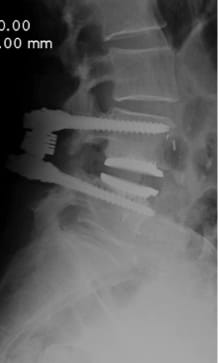

Compared to other implants, the viscoelastic disc prosthesis has the advantage that its design perfectly mimics the function of the natural disc. Furthermore, extensive laboratory testing has proven that it has a durability of at least 50 years. Whether and how surgical treatment of the affected vertebral segments should be carried out is planned individually by the specialist after thorough diagnosis (MRI, CT, X-ray, physical and neurological examination). If, for certain reasons, partial fusion of a section of the spine is unavoidable, this should be limited to one segment as far as possible, as shown in the following example. In this way, the greatest possible functionality of the spine can be maintained or restored.

Postoperative status: Complete axial correction of the lumbar spine with two disc prostheses and a PEEK cage. Normal lordosis of the lumbar spine also visible in the lateral view after the operation. (Spine Centre Rischke)